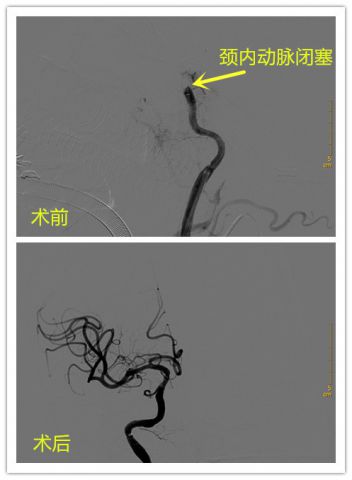

脑血管介入